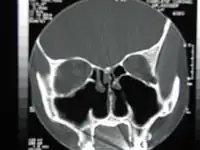

![]() CT scan of the nose after total bilateral turbinectomy/turbinoplasty | |

A turbinectomy or turbinoplasty (preserving the mucosal layer) is a surgical procedure, that removes tissue, and sometimes bone, of the turbinates in the nasal passage, particularly the inferior nasal concha. The procedure is usually performed to relieve nasal obstructions.[1] In most cases, turbinate hypertrophy is accompanied by some septum deviation, so the surgery is done along with septoplasty.[2]